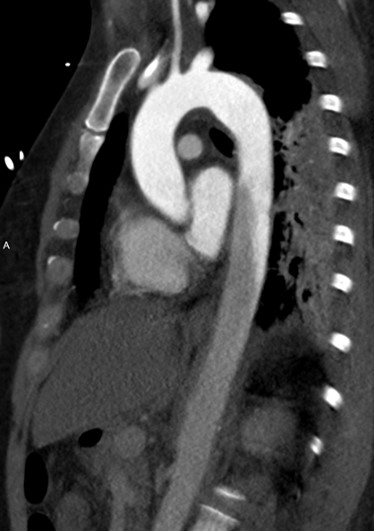

Weird appearance of aorta on CTA. Can easily be confused with dissection, but this is from contrast mixing with blood return in VA ECMO. The 3D image shows ECMO canulae. Several nice references, here's one from Korea https://www.ncbi.nlm.nih.gov/pmc/articles/PMC4023050/ …

#FOAMed#radres pic.twitter.com/doTpBuhMDl